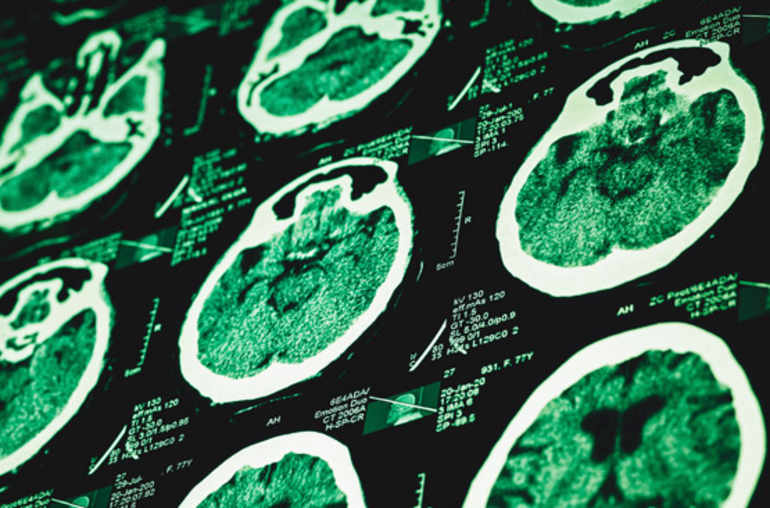

La BBC (Michelle Roberts) en a dit, la première, l’essentiel. On lira ici la lettre publiée par Nature, et ici le commentaire qui lui est associé (Alison Abbott). Les troublantes observations de l’équipe de John Collinge et Sebastian Brandner (Department of Neurodegenerative Disease, UCL Institute of Neurology, Queen Square, London) résultent des observations faites après autopsies cérébrales de huit personnes décédées de la maladie de Creutzfeldt-Jakob (MCJ) et qui avaient été traitées par des hormones de croissance contaminées par un prion pathologique.

Les chercheurs anglais ont retrouvé dans les tissus de quatre de ces cerveaux les mêmes dépôts de protéine bêta-amyloïde (BA) anormale (amylose cérébrale) que ceux que l’on retrouve dans les tissus cérébraux des personnes victimes de la maladie d’Alzheimer. La présence de cette même protéine a été identifiée dans deux autres cerveaux. Or il s’agissait de malades jeunes, âgés de 36 à 51 ans au moment de leur décès, ce qui est excessivement rare (et correspond à la définition de cette démence précoce décrite en Allemagne par Aloïs Alzheimer il y a un siècle).

Les auteurs avancent d’autre part plusieurs arguments solides en faveur d’une transmission interhumaine de la maladie d’Alzheimer. Difficile, pour l’équipe de Collinge et Brandner, de ne pas émettre l’hypothèse d’une contamination des quatre malades via des protéines bêta-amyloïde anormales déjà présentes dans les hypophyses des cadavres à partir desquelles on préparait, jusqu’au début des années 1980, une hormone de croissance extractive.